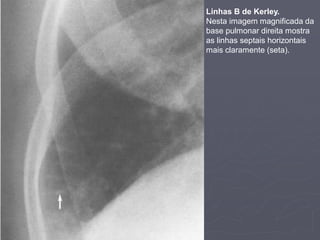

3. Linhas B de Kerley:

1. Procure pelas linhas B de Kerley. Elas são causadas

por edema dos septos interlobulares.

2. Elas são horizontais, sem bifurcação,

hipotransparentes, melhores vistas na periferia do

pulmão logo acima do ângulo costofrênico.

Dr. Emanuel R. Dantas

Linhas B de Kerley.

Nesta imagem magnificada da

base pulmonar direita mostra

as linhas septais horizontais

mais claramente (seta).